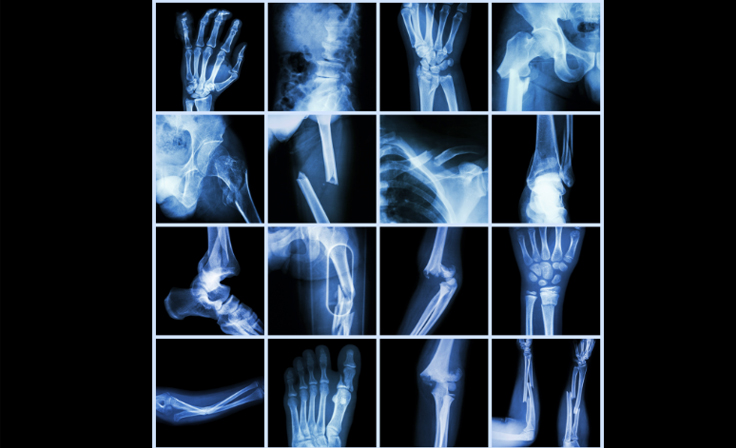

Fracture Management

A fracture, commonly known as a broken bone, occurs when excessive force or trauma causes a bone to crack or break. Fractures can range from minor cracks to severe breaks that require surgical intervention. Proper management is essential to ensure healing, restore function, and prevent complications.

Fracture locations and their management approaches